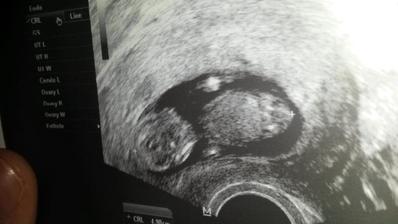

26dpo kvůli špinění 1uzv potvrzen váček a žl.tělísko v děloze)

16.12.2015 ( 31dpo) uzv v Ol u p.Poláka... srdíčko bije 🙂